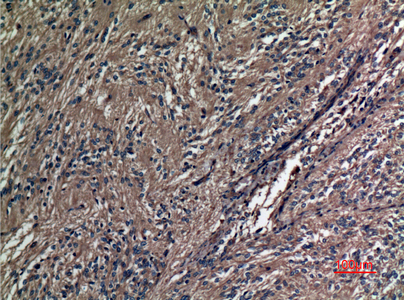

分类: 科研抗体货号: P23533别名: Prominin-1; Antigen AC133; Prominin-like protein 1; CD133.应用: WB,IHC反应种属: Human,Mouse